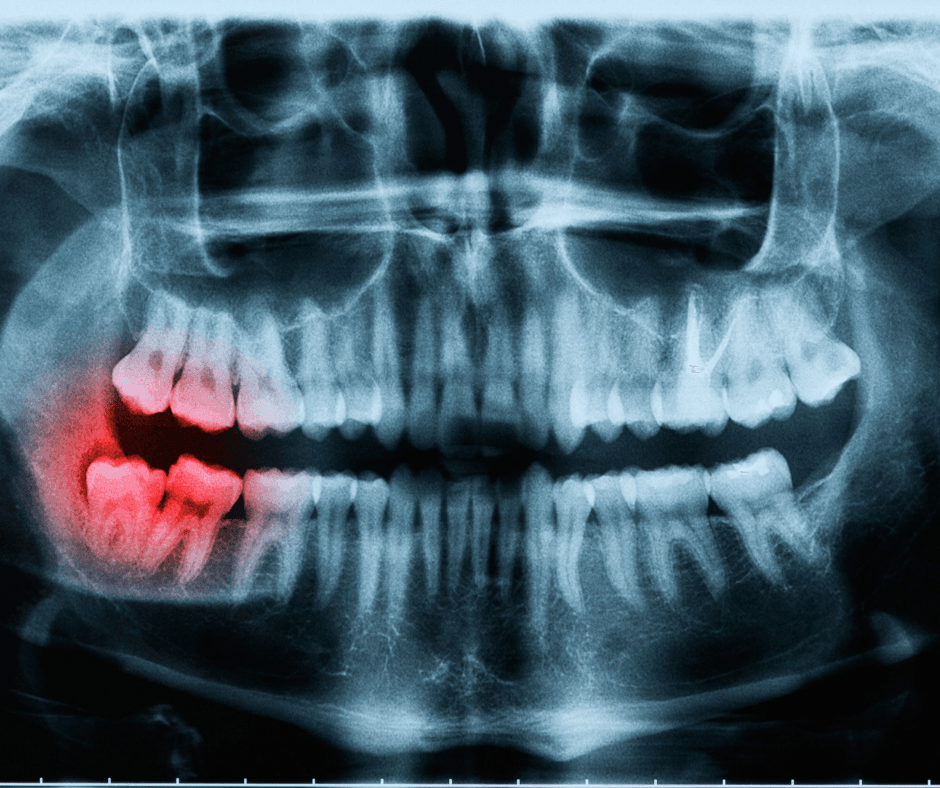

Why do we have wisdom teeth?